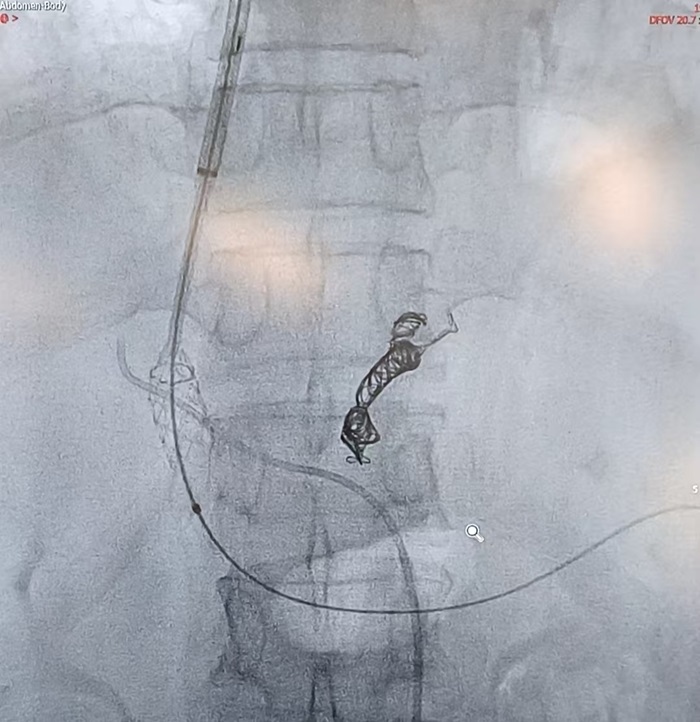

经肝静脉穿刺门静脉成功

支架释放